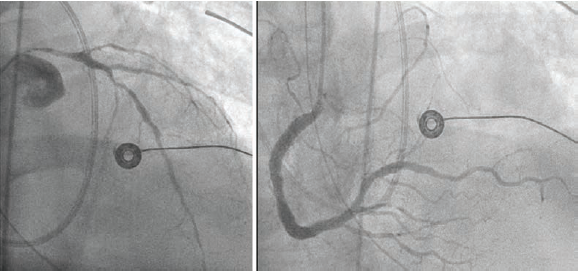

At the outlying hospital, the patient underwent invasive coronary angiography that demonstrated severe multivessel coronary artery disease involving the entire left main coronary artery, severe diffuse disease in the left anterior descending artery (LAD), and a chronic total occlusion of the circumflex artery with right-to-left collateral flow from the distal right coronary artery that had mild-moderate stenosis in the mid segment. An intra-aortic balloon pump (IABP) was implanted via right common femoral access (Figure 1).

A 6 French right radial access was obtained and the left main coronary artery (LMCA) was cannulated. The first diagonal branch was wired and the LAD was wired with a second wire. Pre-dilation from the mid LAD back into the LMCA was performed with 2.0 x 20 mm semicompliant balloon. Intravascular ultrasound (IVUS) was then performed with the Refinity short-tip rotational IVUS catheter (Philips) in the mid LAD into the LMCA, and demonstrated fibrocalcific plaque with segments of circumferential calcium (Figure 2). The distal reference diameter was measured as 3.4 mm in the LAD and proximal reference diameter as 4.2 mm in the LMCA (Figure 3).